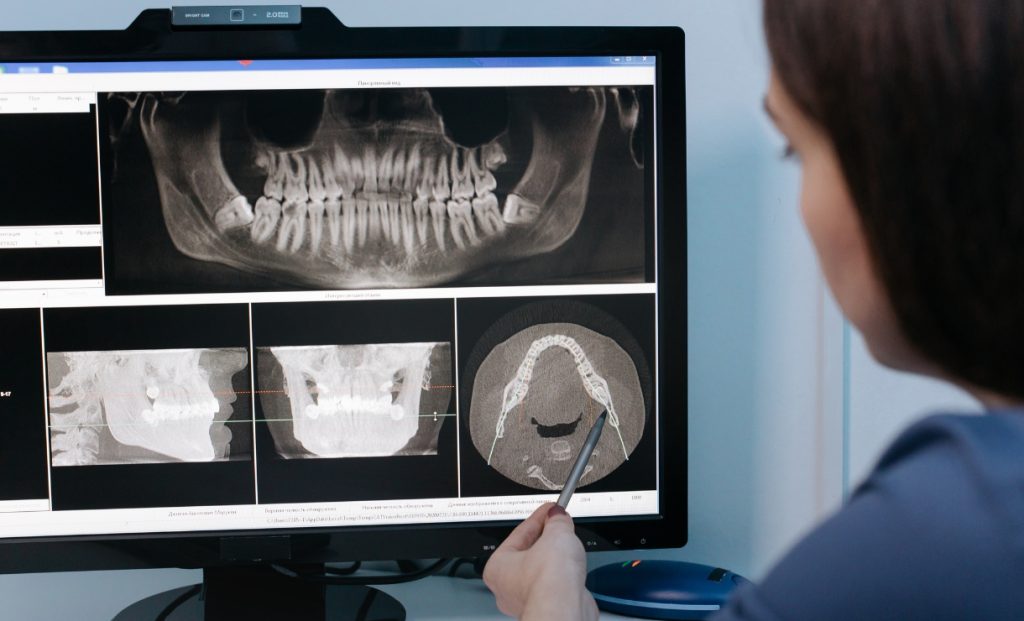

A articulação temporomandibular é uma das estruturas mais complexas e funcionalmente exigidas do corpo humano. Localizada entre o osso temporal do crânio e a mandíbula, essa articulação desempenha um papel essencial em funções cotidianas como falar, mastigar, engolir e realizar movimentos faciais. Sempre que abrimos ou fechamos a boca, essa articulação entra em ação de […]